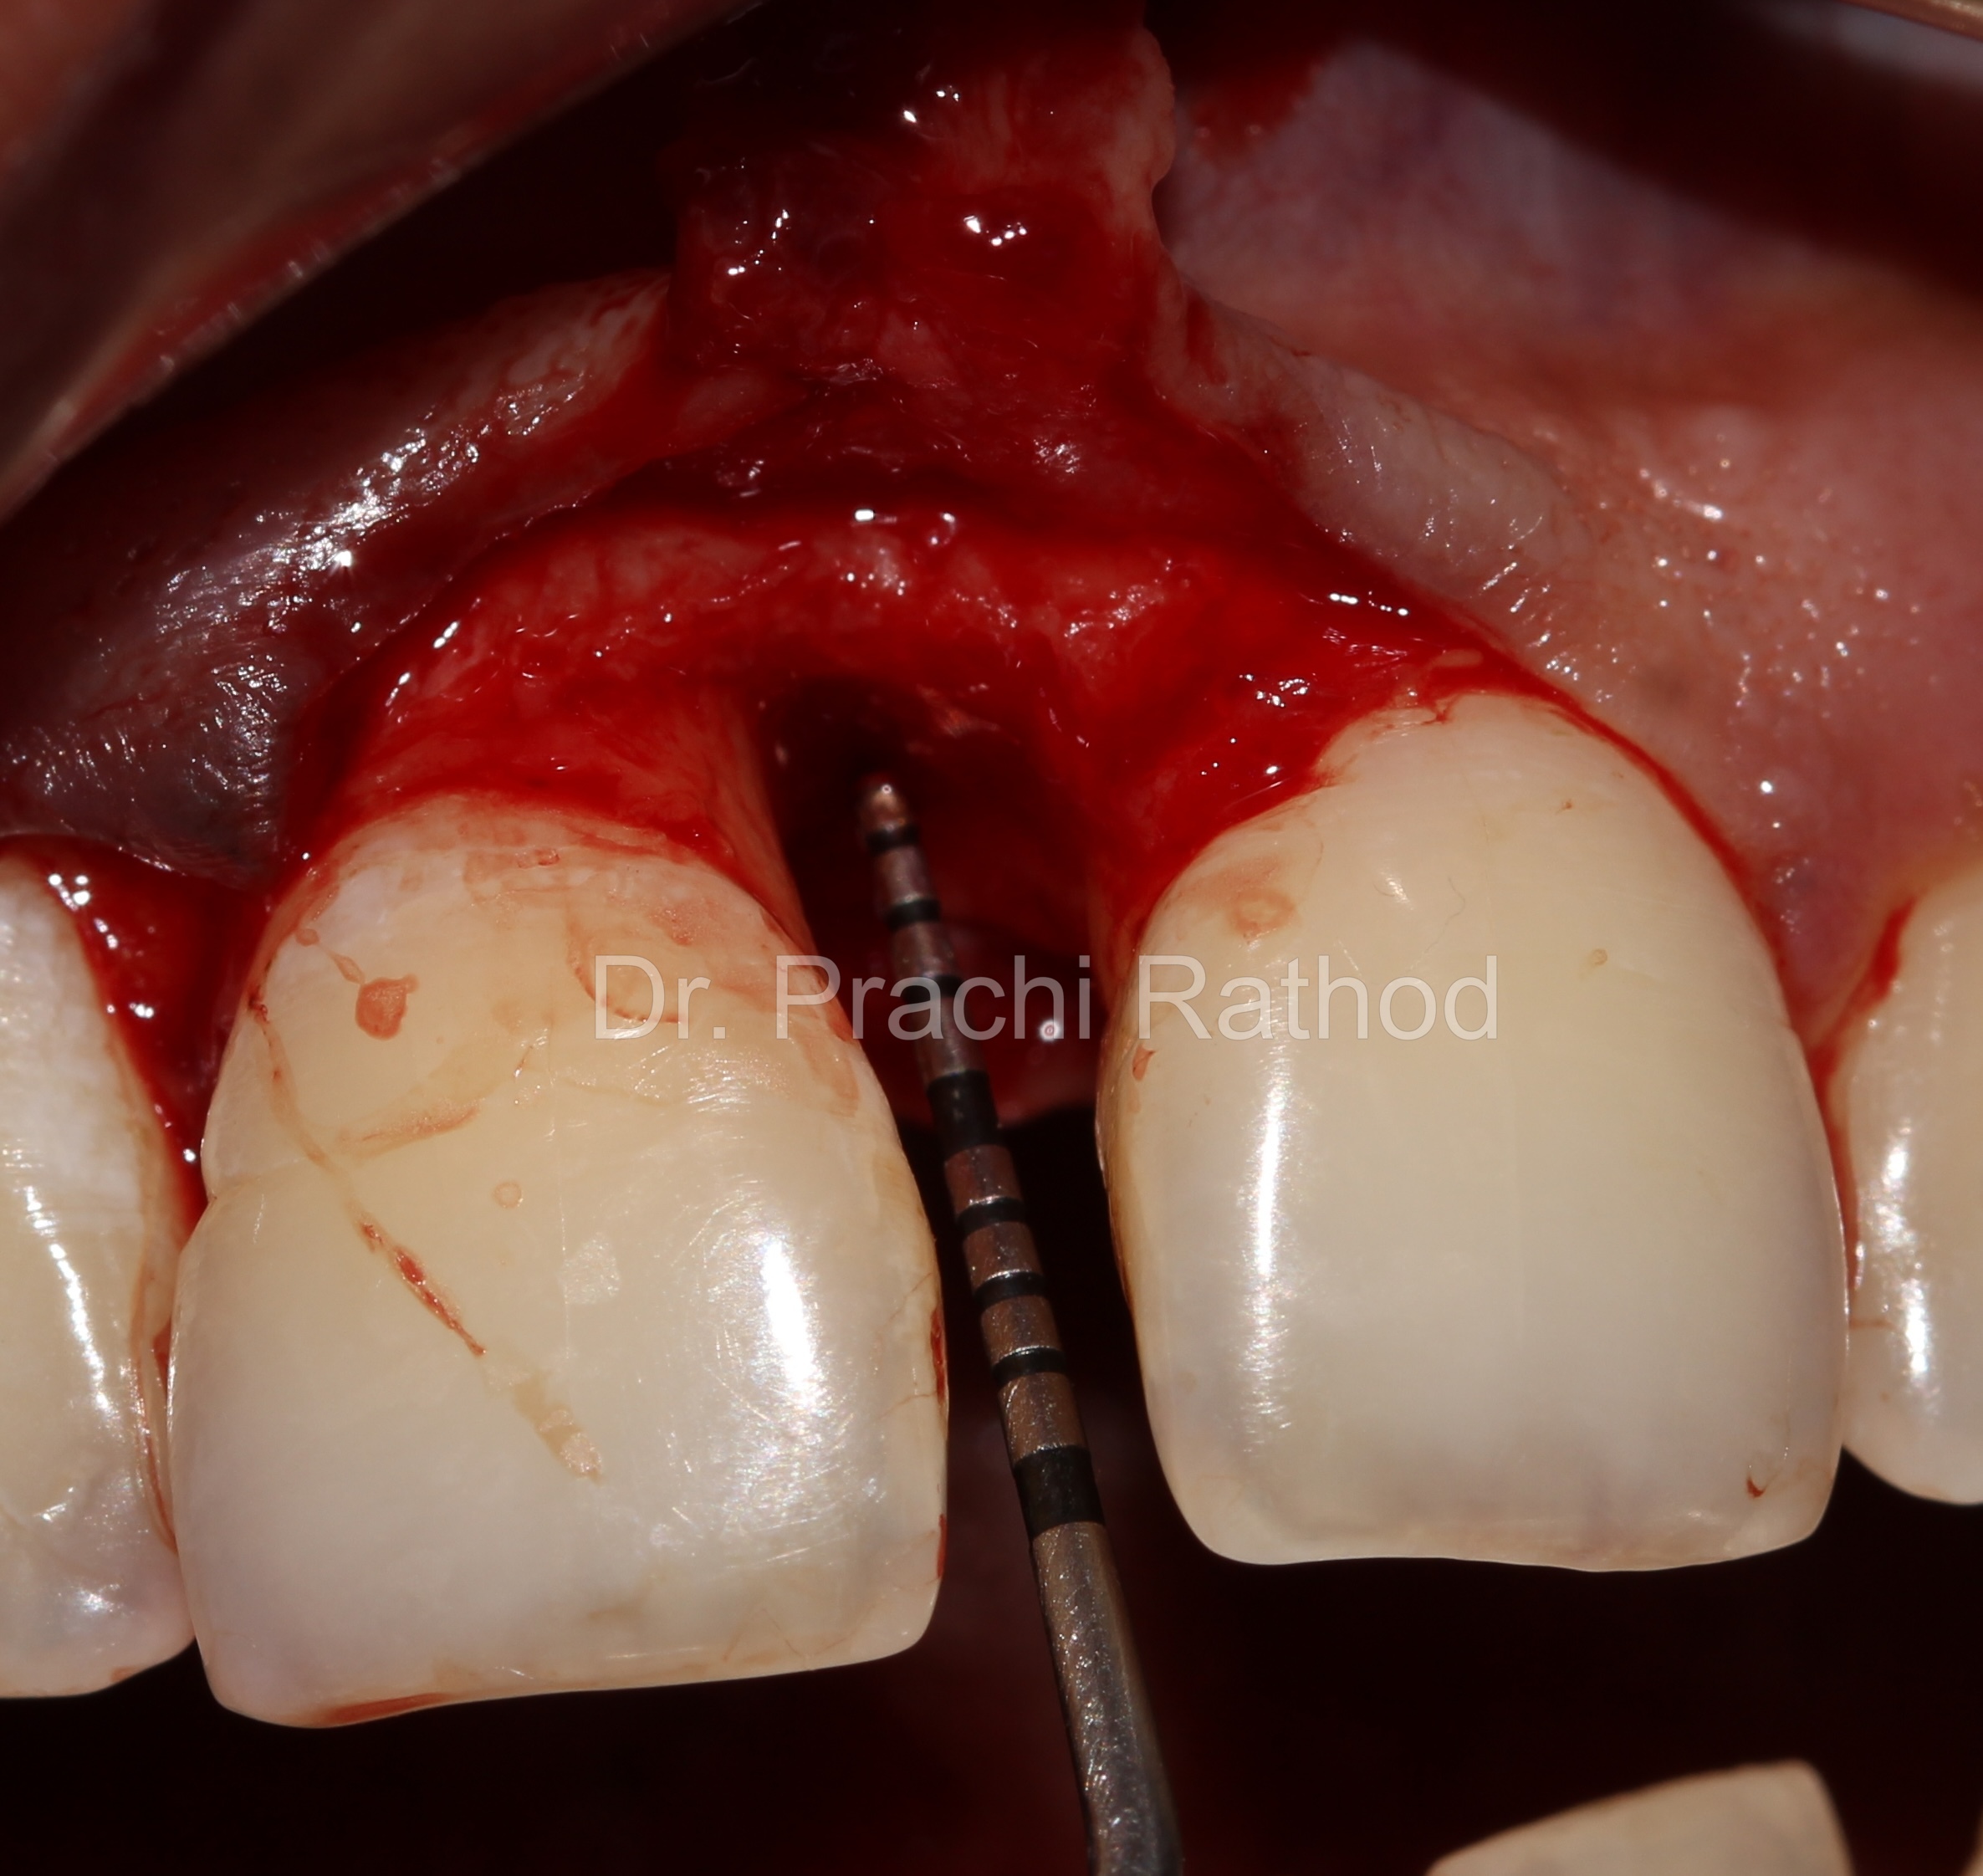

Pre Op Pocket Depth Probing